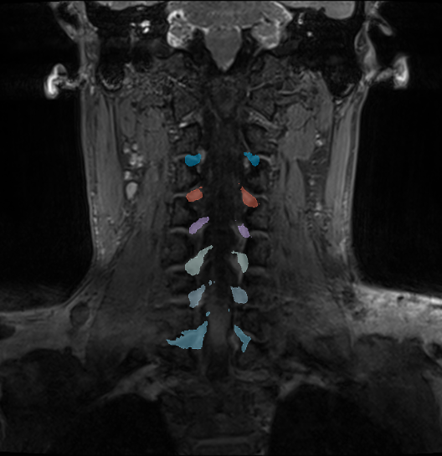

AI-powered precision imaging of the cervical spine